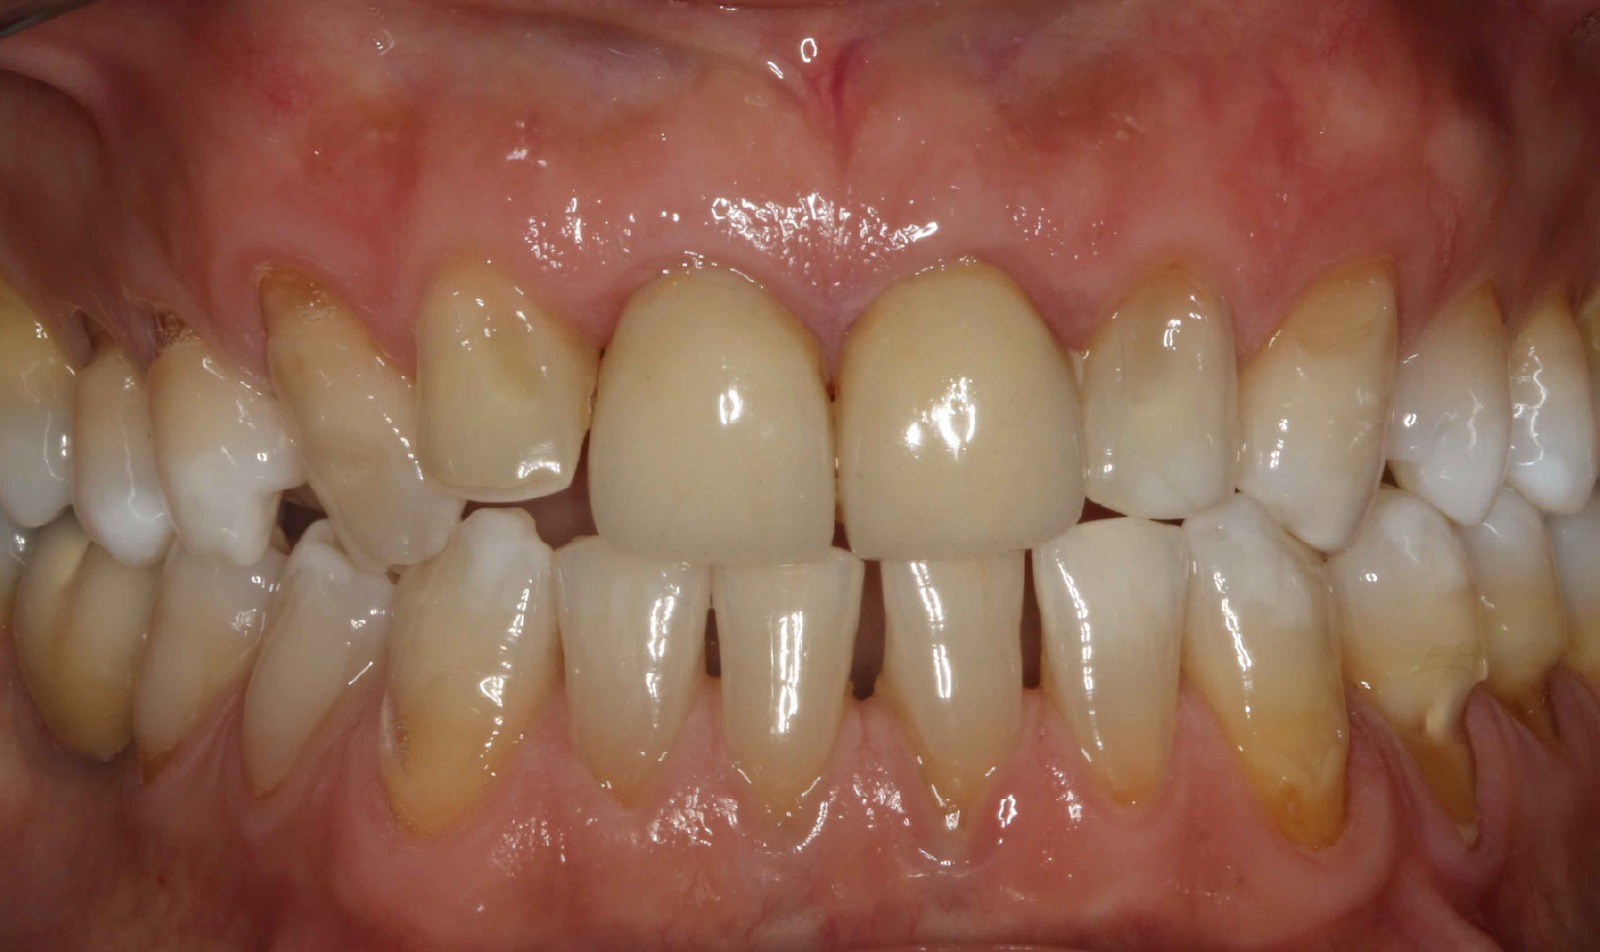

Injerto de encía para solucionar recesión

BeforeAfter